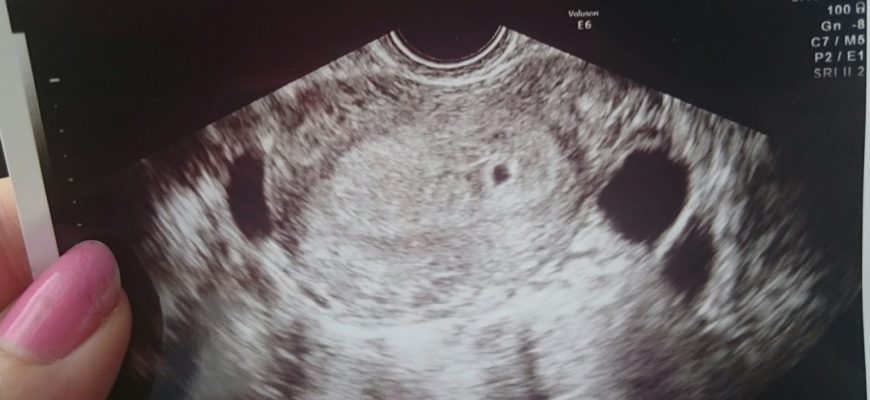

Ультразвуковая диагностика плода

На 4 неделе беременности ультразвуковое исследование позволяет специалисту четко увидеть желтое тело, которое постоянно увеличивается в размерах. Его роль заключается в питании эмбриона до тех пор, пока плацента не станет стабильной. Это образование также производит прогестерон, гормон, который помогает поддерживать беременность.

Современное оборудование позволяет легко определить наличие эмбриона, прикрепленного к стенке матки. УЗИ на таком маленьком сроке беременности проводится очень редко. Будущие мамы не всегда знают о своем состоянии, либо просто делают тест на беременность.

С учетом того, что сердце формируется впервые, на 4-й неделе от зачатия уже можно услышать его работу на аппаратах УЗИ. Но это только на современных машинах.

Сам плод в этот период развития врачи называют эмбрионом. Размер около 2 мм, длина 5 мм.